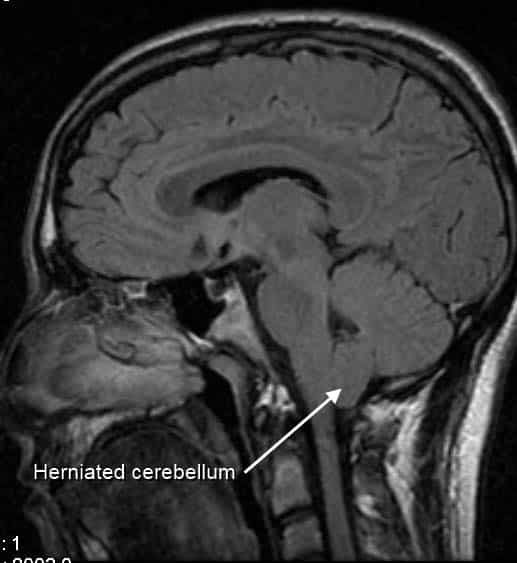

The floor of the cranial cavity is divided into three distinct depressions. They are known as the anterior cranial fossa, middle cranial fossa and posterior cranial fossa. Each fossa accommodates a different part of the brain. The posterior cranial fossa is the most posterior and deep of the three cranial fossae. It accommodates the brainstem and cerebellum. In this article, we shall look at the borders, contents and clinical correlations of the posterior cranial fossa. Pro Feature - 3D Model You've Discovered a Pro Feature Access our 3D Model Library Explore, cut, dissect, annotate and manipulate our 3D models to visualise anatomy in a dynamic, interactive way. Learn More Borders The posterior cranial fossa is comprised of three bones: the occipital bone and the two temporal bones. It is bounded as follows: Anteromedial – dorsum sellae of the sphenoid bone (large projection of bone superiorly that arises from the body of the sphenoid). Anterolateral – superior border of the petrous part of the temporal bone. Posterior – internal surface of the squamous part of the occipital bone. Floor – mastoid part of the temporal bone and the squamous, condylar and basilar parts of the occipital bone. By TeachMeSeries Ltd (2025) Fig 1The bones of the cranial floor. The posterior cranial fossa has been outlined.Fig 1.0 – The bones of the cranial floor. The posterior cranial fossa has been outlined. Contents The posterior cranial fossa houses the brainstem and cerebellum. The brainstem is comprised of the medulla oblogata, pons and midbrain and continues down through the foramen magnum to become the spinal cord. The cerebellum has an important role in co-ordination and fine motor control – more information here. Alongside the gross anatomical structures of the brainstem and cerebellum, the posterior cranial fossa also accommodates associated arteries and nerves. Some key structures will be discussed with regards to their foramina below. Foramina There are several bony landmarks and foramina present in the posterior cranial fossa (a foramen is simply a hole that allows the passage of a structure – usually a blood vessel or nerve). Temporal Bone The internal acoustic meatus is an oval opening in the posterior aspect of the petrous part of the temporal bone. It transmits the facial nerve (CN VII), vestibulocochlear nerve (CN VIII) and labyrinthine artery. Occipital Bone A large opening, the foramen magnum, lies centrally in the floor of the posterior cranial fossa. It is the largest foramen in the skull. It transmits the medulla of the brain, meninges, vertebral arteries, spinal accessory nerve (ascending), dural veins and anterior and posterior spinal arteries. Anteriorly an incline, known as the clivus, connects the foramen magnum with the dorsum sellae. The jugular foramina are situated either side of the foramen magnum. Each transmits the glossopharyngeal nerve, vagus nerve, spinal accessory nerve (descending), internal jugular vein, inferior petrosal sinus, sigmoid sinus and meningeal branches of the ascending pharyngeal and occipital arteries. Immediately superior to the anterolateral margin of the foramen magnum is the hypoglossal canal. It transmits the hypoglossal nerve through the occipital bone. Posterolaterally to the foramen magnum lies the cerebellar fossae. These are bilateral depressions that house the cerebellum. They are divided medially by a ridge of bone, the internal occipital crest. By TeachMeSeries Ltd (2025) Fig 2The bony landmarks and foramina of the posterior cranial fossa. Clinical Relevance Cerebellar Tonsillar Herniation Cerebellar tonsillar herniation is the downward displacement of the cerebellar tonsils through the foramen magnum. It is also known as ‘coning’. It is produced by a raised intracranial pressure, which has a varied aetiology. Causes include hydrocephalus, space occupying lesions, and a malformed posterior cranial fossa. Cerebellar tonsillar herniation results in the compression of the pons and medulla, which contain the cardiac and respiratory centres. Thus, a herniation of this type ultimately results in death from cardiorespiratory arrest. By Basket of Puppies (Own work) [CC-BY-SA-3.0] via Wikimedia Commons Fig 3Sagittal MRI imaging of the head, demonstrating cerebellar tonsil herniation. Do you think you’re ready? Take the quiz below Pro Feature - Quiz The Posterior Cranial Fossa Question 1 of 3 Submitting... Skip Next Rate question: You scored 0% Skipped: 0/3 1800 More Questions Available Upgrade to TeachMeAnatomy Pro Challenge yourself with over 1800 multiple-choice questions to reinforce learning Learn More Rate This Article